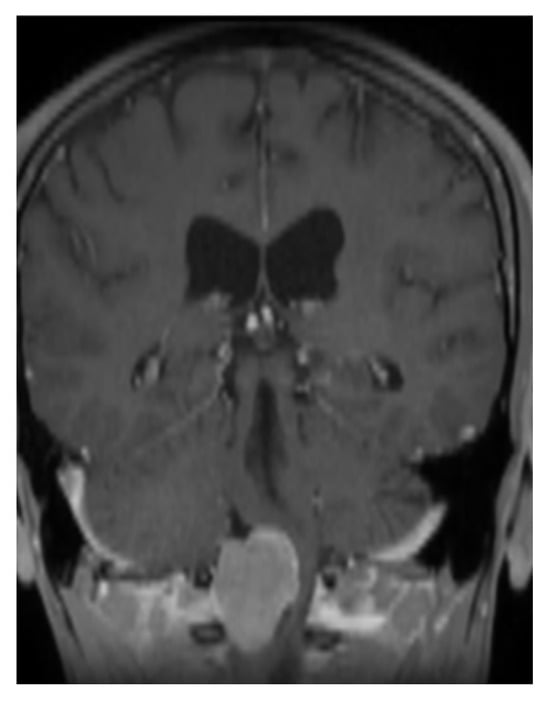

Case Report